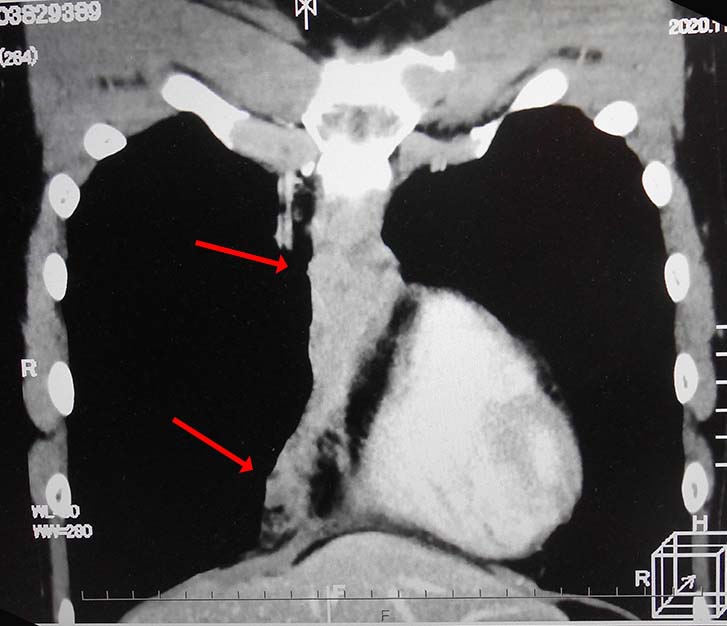

無痛性精巣腫大で泌尿器科受診. 画像診断では, 左精巣最大径4.5cmの腫瘤で縦隔リンパ節転移が疑われた. 左高位精巣摘除術をうける.